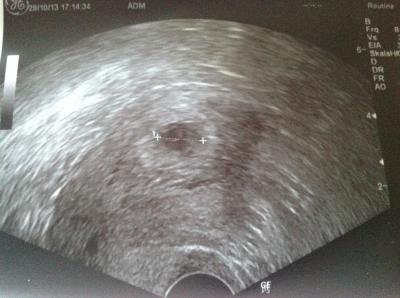

Kann es kaum glauben, gestern Abend war ich nochmal zur Kontrolle wegen meiner starken Blutung und den heftigen Schmerzen am Freitag. Selbst der Doc hat seinen Augen kaum glauben können, als da eine Fruchtsack mit Inhalt zu erkennen war. Am Freitag war es ein trichterförmiges, fruchtsack ähnliches Gewebe im Abgang und nun sieht es aus als wäre nichts passiert. Ich hatte ein riesiges Hämatom was auch noch sehr stark zu erkennen ist (rechts). Auch der HCG Wert ist 3 mal so hoch gestiegen seit Freitag auf 10.000. Leider ist das Hämatom immer noch ca. 4 x 1,5 cm und es kann jeder Zeit wieder zu Blutungen und Wehen kommen und deswegen ist jetzt Bettruhe angesagt. Bin erstmal bis zur nächsten Untersuchung am Mittwoch nächste Woche krankgeschrieben und als Aufgabe, soll ich bis dahin ganz viele Herzschläge mit bringen. Das ist schlimmer als Achterbahn fahren. Meine Nerven....

Bild zu Es war/ist ein Hämatom, das Baby ist noch da !!!!! - Kinderwunschbehandlung